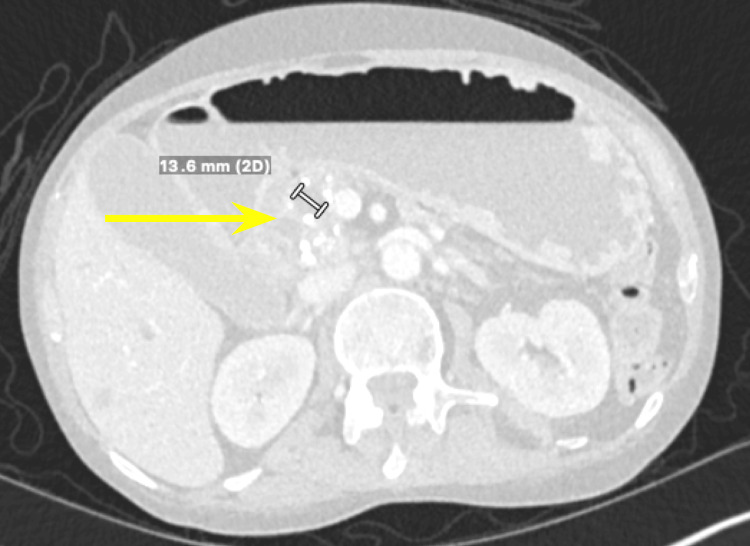

We present a case of a 68-year-old male with a past medical history of prostate cancer requiring radical prostatectomy, hypertension, hyperlipidemia, alcohol use disorder, and 50-pack-year smoking history who presented with several weeks of anorexia, dyspnea on exertion, generalized weakness, nausea, and vomiting. He also noted an unintentional 20-pound weight loss over the last several months. Vital signs were within normal limits with blood pressure of 118/80 mmHg, pulse of 98 beats per minute, respiratory rate of 16 while saturating 100% on room air, and temperature of 98.8°F. Physical exam was remarkable for a cachetic, ill-appearing male in no acute distress. Laboratory evaluation was significant for acute kidney injury (creatinine (Cr) of 2.89 mg/dL from baseline of 0.5-0.6 mg/dL; reference range: 0.51-0.96 mg/d), mild transaminitis with aspartate transferase (AST) of 46 IU/L (reference range: 14-33 IU/L), anion gap of 28 mmol/L (reference range: 4-16 mmol/L), lactic acidosis of 8 mmol/L (reference range: <2 mmol/L), and beta-hydroxybutyrate of 4 mmol/L (reference range: 0.5 mmol/L). CT of the abdomen and pelvis showed three main findings. The first was a large 6.0 cm heterogeneous mass located in the second portion of the duodenum and pancreatic groove (Figures 1–2).

Additionally, there were multiple coarse calcifications throughout the pancreas, consistent with CP (Figure 3). Lastly, the mass was causing significant dilation of the pancreatic (Figure 4), intrahepatic, and extrahepatic biliary ducts.

Tumor markers including cancer antigen 19-9 (CA 19-9), carcinoembryonic antigen (CEA), and alpha-fetoprotein were all within normal limits. Multiple lymph nodes were enlarged, with the peripancreatic and mesenteric lymph nodes being greater than 8 mm and the portacaval lymph node measuring 9 mm. Furthermore, there was a lesion noted on the liver (Figure 5), later classified through liver MRI as a benign hemangioma.